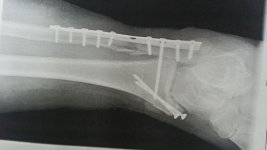

Narkose habe ich direkt an Tunnelrutsche bekommen. 30 min später lag auf OP Tisch. Am 6.07. ist der Stellschraube entfernt.

Vollbelastung erlaubt. Jetzt ca 4 Wochen später kann immer noch nicht der Fuß voll belasten.keine 100 & Pro- und Supination ,keine 100 % Abrollbewegung, Reduktion der Schwellung minimal,muskuläre Dysbalancen v. a. im Unterschenkelbereich . Kühlen tue ich z. Zeit gar nicht ,es schmerzt .